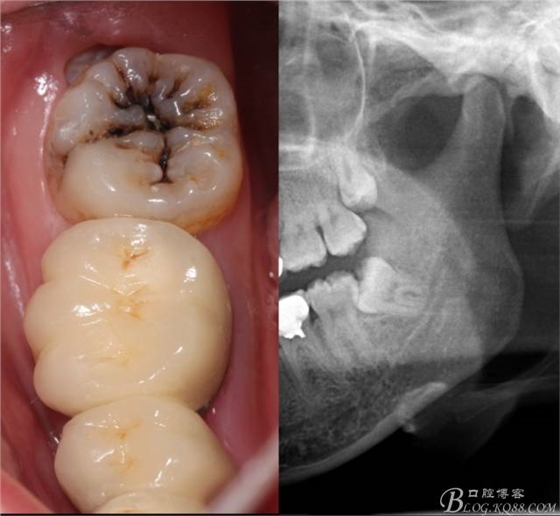

檢查:(1)37牙合面齲,卡探針. (2)38近中埋伏阻生

X全景片示38近中三類阻生,非融合根,近中根壓下頜管,37遠(yuǎn)中鄰面中齲樣影像。

診斷:(1)37中齲 (2)38近中阻生

治療建議:37齲修復(fù)后撥除38.

先分析智齒的情況,口內(nèi)直觀是半個(gè)牙尖都沒露出來,差一點(diǎn)就完全埋伏了。磨牙后墊的可操作面積中規(guī)中紀(jì),X全景片示三類阻生,根冠比例是1:1,非融合根,近中根壓下頜管。